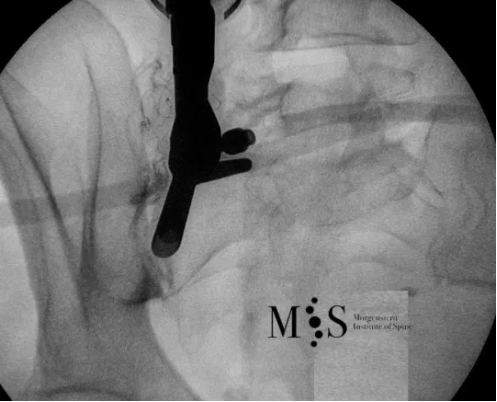

Example of an intra-articular infiltration of the right sacroiliac joint

Dr. Morgenstern performs intra-articular infiltrations of the sacroiliac joint using a new intra-articular infiltration technique developed in German that allows the joint to be infiltrated on an outpatient basis, without the need of contrast medium and operating room (which are usually necessary for other, popular infiltration techniques).

The analgesic effects of the SI joint infiltration are usually immediate. Still, two infiltrations are usually recommended with a time interval of 2 to 3 weeks in order to significantly reduce inflammation of the affected sacroiliac joint and decrease the pain for a long period of time.